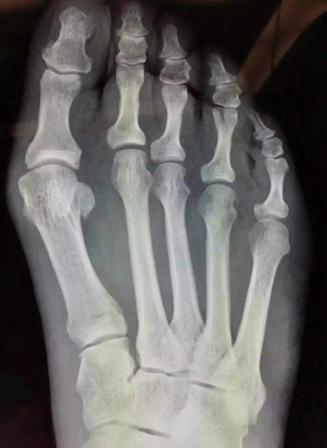

拇外翻畸形是指拇趾向外侧偏斜移位引起的畸形,内侧突起部位常常发生拇囊炎。拇外翻是累及拇趾的最常见的病变,多见于中老年妇女,女性发病是男性的9倍,常有遗传倾向,加上长时间穿不合适的鞋子,鞋子会对拇趾施加异常压力,最终发生拇外翻畸形。

根据拇趾外翻程度和拇外翻测量角的不同,可以分为轻、中、重度三种类型。